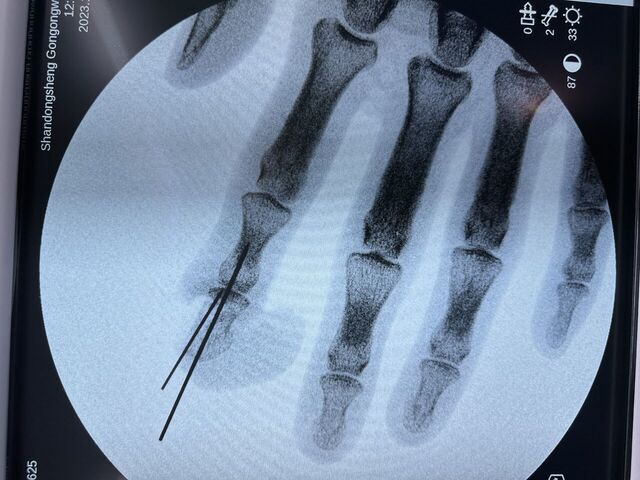

下面是一例示指再造,术后一年10个月随访

微信图片_20230930083837.jpg 微信图片_20230930083849.jpg 微信图片_20230930083851.jpg 微信图片_20230930083851_1.jpg

术后骨折愈合良好